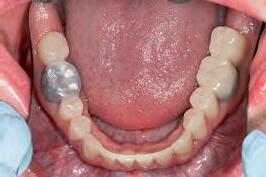

The patient was an 18-year-old male with a confirmed family history of Xlinked AI, who was otherwise in good health and non-smoking. Upon initial clinical presentation, a low-caries-risk, complete adult dentition from second molar to second molar was present, which was globally affected by pitted, hypoplastic and hypomineralised AI, dento-alveolar disproportion and an unusual generalised open occlusion, characterised by one occlusal contact at the right first molar region in the maximum intercuspation position (MIP). Historical paediatric management of the dentition involved placement of stainless steel crowns at the first permanent molar sites to protect the emerging dentition from post-eruptive breakdown and loss of occlusovertical dimension during the mixed dentition phase.6 On adult presentation, all but the UR6 stainless steel crown remained intact. Oral hygiene was poor, with evidence of plaque-induced chronic gingivitis (Figure 1). The patient reported experiencing severe, widespread hypersensitivity upon hot, cold, osmotic and masticatory stimuli, and feeling aesthetically self-conscious. The patient was seeking comprehensive fixed prosthodontic care and was well informed about the nature of such treatment, having witnessed his elder siblings undergo similar treatment.

1: The patient’s initial situation on clinical presentation to the tertiary care referral centre. The dentition is globally af fected by amelogenesis imperfecta, associated with dentoalveolar disproportion and an unusual presentation of open occlusion.